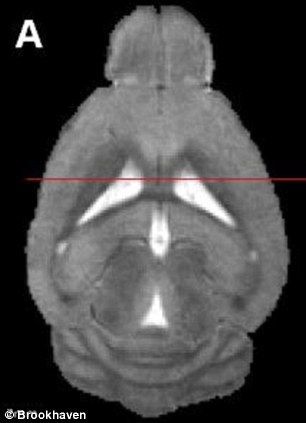

为植入假记忆,研究人员设计了老鼠大脑中控制回忆的细胞。

一开始,研究人员把老鼠放在一个盒子里,让它们感到安全。然后,他们对准储存老鼠身在何处的记忆的大脑细胞,在光中设计这些细胞,使它们“打开记忆”。第二天,他们把这只老鼠放在第二个盒子中,用光脉冲恢复第一天的记忆。记忆重放时,他们适度电击老鼠,希望改变它们的记忆。结果,他们做到了。把老鼠放回第一个盒子时,它们吓得不敢动弹。

这些科学家说,这意味着它们在第一个盒子的记忆成功改变,使它和电击痛苦联系在一起。换句话说,假记忆植入大脑。他们表示:“在这项研究中,我们相信我们第一次成功把假记忆植入老鼠大脑。”他们的实验还显示,虚假和真实记忆触发许多相同的大脑区域,使它们难以区分。